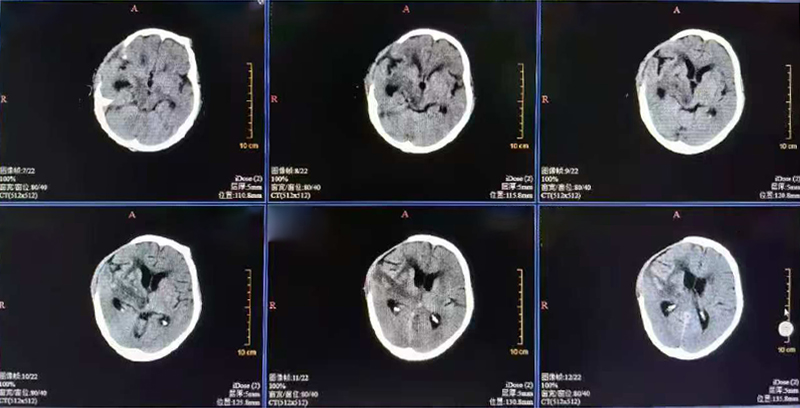

术后